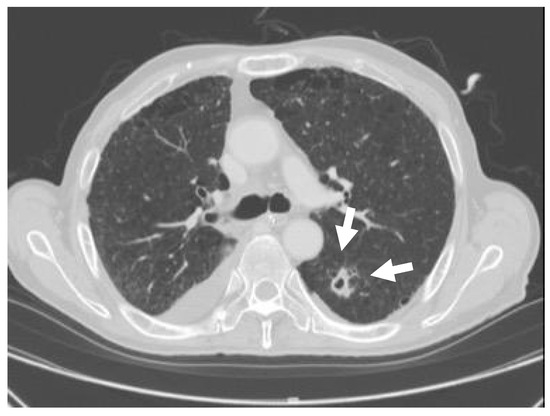

Figure 3.

Cavitary nodule. The CT depicted a 20 mm cavitary nodule in the left lung S6.